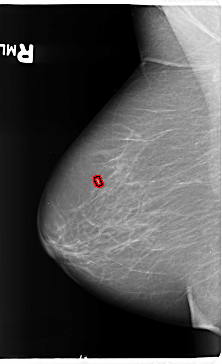

B_3140_1.RIGHT_MLO

FILE: B_3140_1.RIGHT_MLO.OVERLAY

TOTAL_ABNORMALITIES 1

ABNORMALITY 1

LESION_TYPE MASS SHAPE ROUND MARGINS CIRCUMSCRIBED

ASSESSMENT 4

SUBTLETY 4

PATHOLOGY BENIGN

TOTAL_OUTLINES 1

BOUNDARY